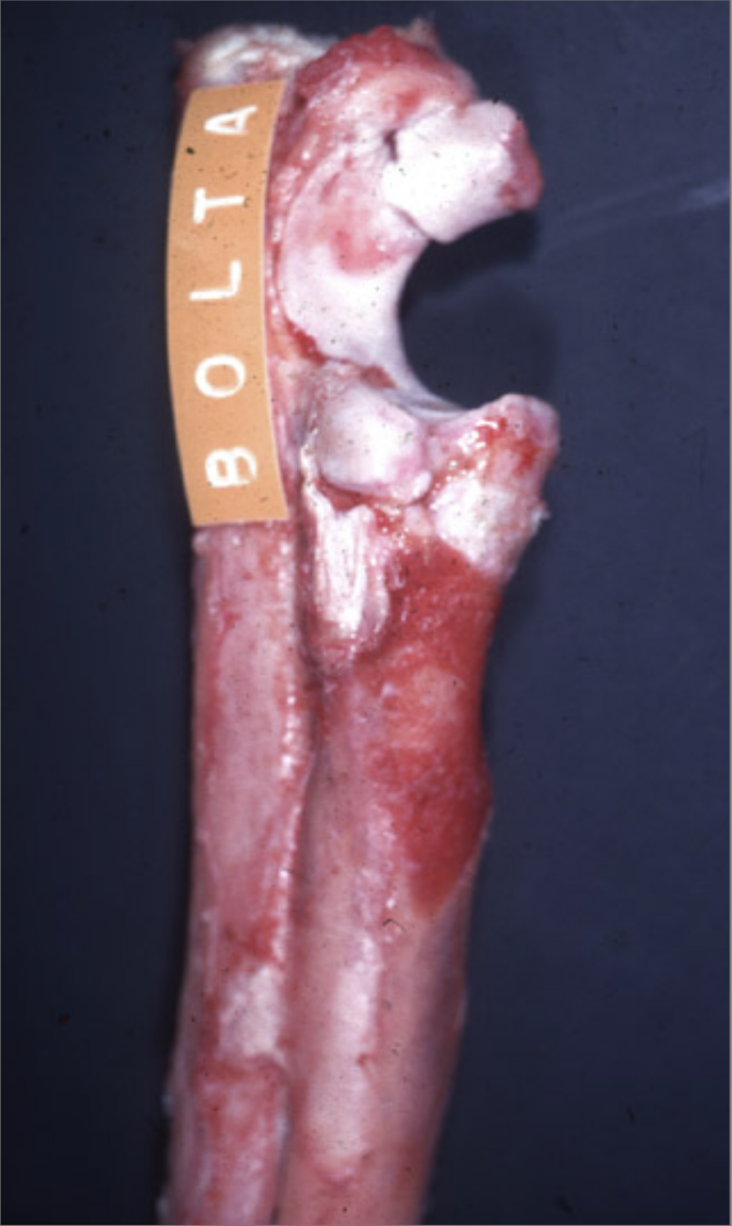

This was taken from a 7 month German Shepherd.

What could cause the lesion presented?

Developmental

What is the name of the lesion shown?

Ununited anconeal process